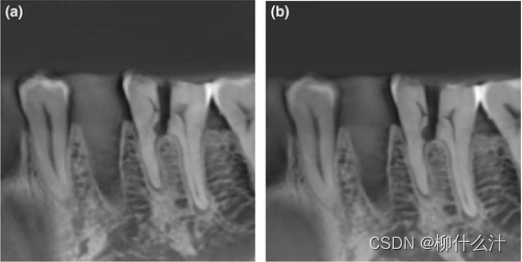

虽然每种cbct设备的基本采集原理是相同的,但在比较采集方法和参数时,重要的差异是显而易见的。首先可以区分的是脉冲式和连续式曝光,脉冲和连续曝光都容易受到探测器滞后的影响,但脉冲更可能表现出更好的空间分布率,因为运动效应减少。其次是旋转角度,大多数cbct扫描仪都是360°获得投影,但是由于机械障碍,全旋转是无法做到的,所以会采取半旋转,此时可以重建出完整的FOV.但是由于头颈部对辐射敏感分布的器官分布不均匀,如骨组织的体积自我衰减和软组织的难以显影。就图像质量而言,部分旋转往往会降低整体图像质量,根据毫安的不同,180°旋转方案比360°方案会导致噪音的轻微或更明显的增加,与较短的扫描相关的采样减少也会导致较短的扫描的图像质量下降(即使总的扫描毫安数是相同的),明显的是与较少的投影数相关的视图混叠效应略有增加。视图混叠效应往往是次要的,而短扫描与360°扫描的全面特征,以及起始角度对图像质量的影响(或没有影响)还没有得到全面评估。

在(a)360°旋转,70毫安和(b)180°旋转,36毫安的情况下,下颌骨的CBCT扫描显示几乎没有可感知的差异。在较低的毫安水平下,差异会更明显。